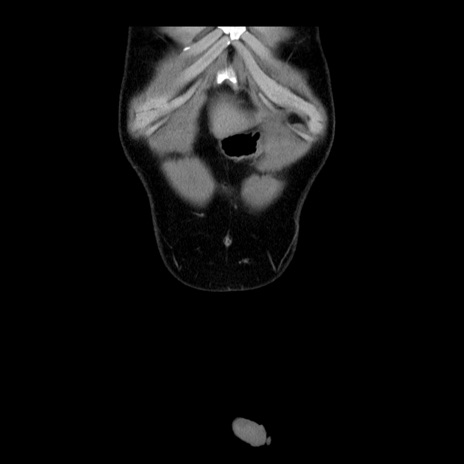

症例4(冠状断像)

【症例】30歳代男性

【主訴】腹痛、嘔吐

【現病歴】昨晩から突然の腹痛あり、その後嘔吐、軟便も出現。腹痛が改善しないため救急搬送となる。2日前にしめ鯖の食事歴あり。

【身体所見】意識清明、苦悶様、BP 135/90mmHg、BT 35.7℃、腹部:平坦、やや硬、心窩部〜臍部に自発痛、圧痛あり、筋性防御+、反跳痛-

【データ】WBC 8100、CRP 0.57